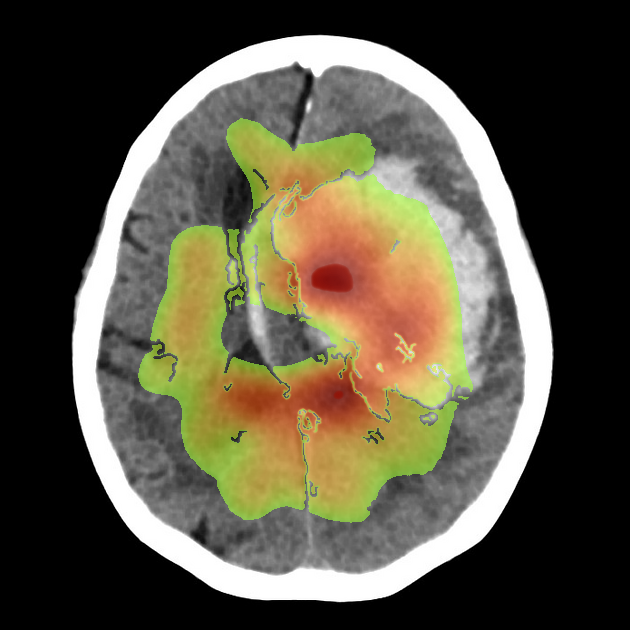

- Large hyperdense intra-axial hematoma centered in the basal ganglia region on the image-right (patient-left).

- Dimensions appear to exceed 4 cm in maximal diameter, consistent with a high-volume hemorrhage.

- Marked surrounding low-density area representing vasogenic edema.

- Significant mass effect with compression of the ipsilateral lateral ventricle and effacement of cortical sulci.

- Midline shift of approximately 8–10 mm towards the image-left (patient-right).

- Deformation and partial effacement of the third ventricle, raising concern for obstructive hydrocephalus.

- No extra-axial hemorrhage evident in this slice.

The most likely diagnosis is a large acute intracerebral hemorrhage involving the image-right (patient-left) basal ganglia. This is supported by the hyperdense appearance of acute blood, classic deep location, and associated edema with mass effect. Hypertensive intracerebral hemorrhage is the most common etiology, especially in the basal ganglia region. The degree of shift and ventricular compression indicates a life-threatening presentation.